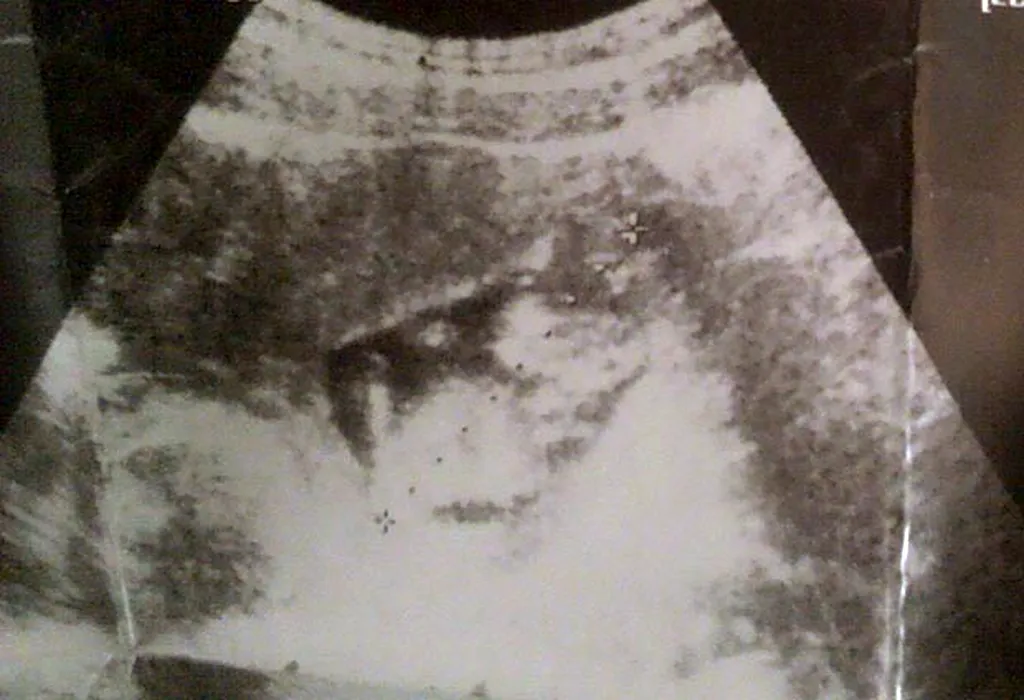

„Mi-era teamă să fac un copil, așa că am recurs la avort”. TOCOFOBIA, boala femeilor cărora le este frică de sarcină